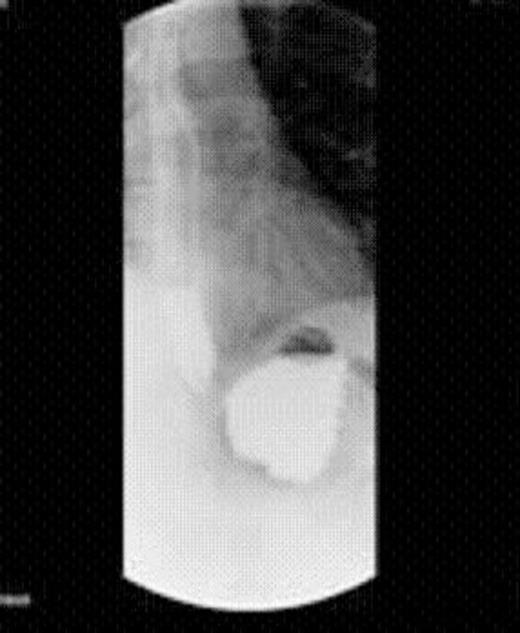

The patient was discharged home the next day. Six weeks after the procedure, the patient had lost 12kg in weight and no longer complained of any dumping syndrome. An upper GI series x-ray obtained 2 months after the pouch plication procedure revealed reduction in the size of the gastric pouch and a delay in emptying of contrast from the gastric pouch into the jejunum.

Upper GI Series 2 months after endoluminal gastric pouch plication